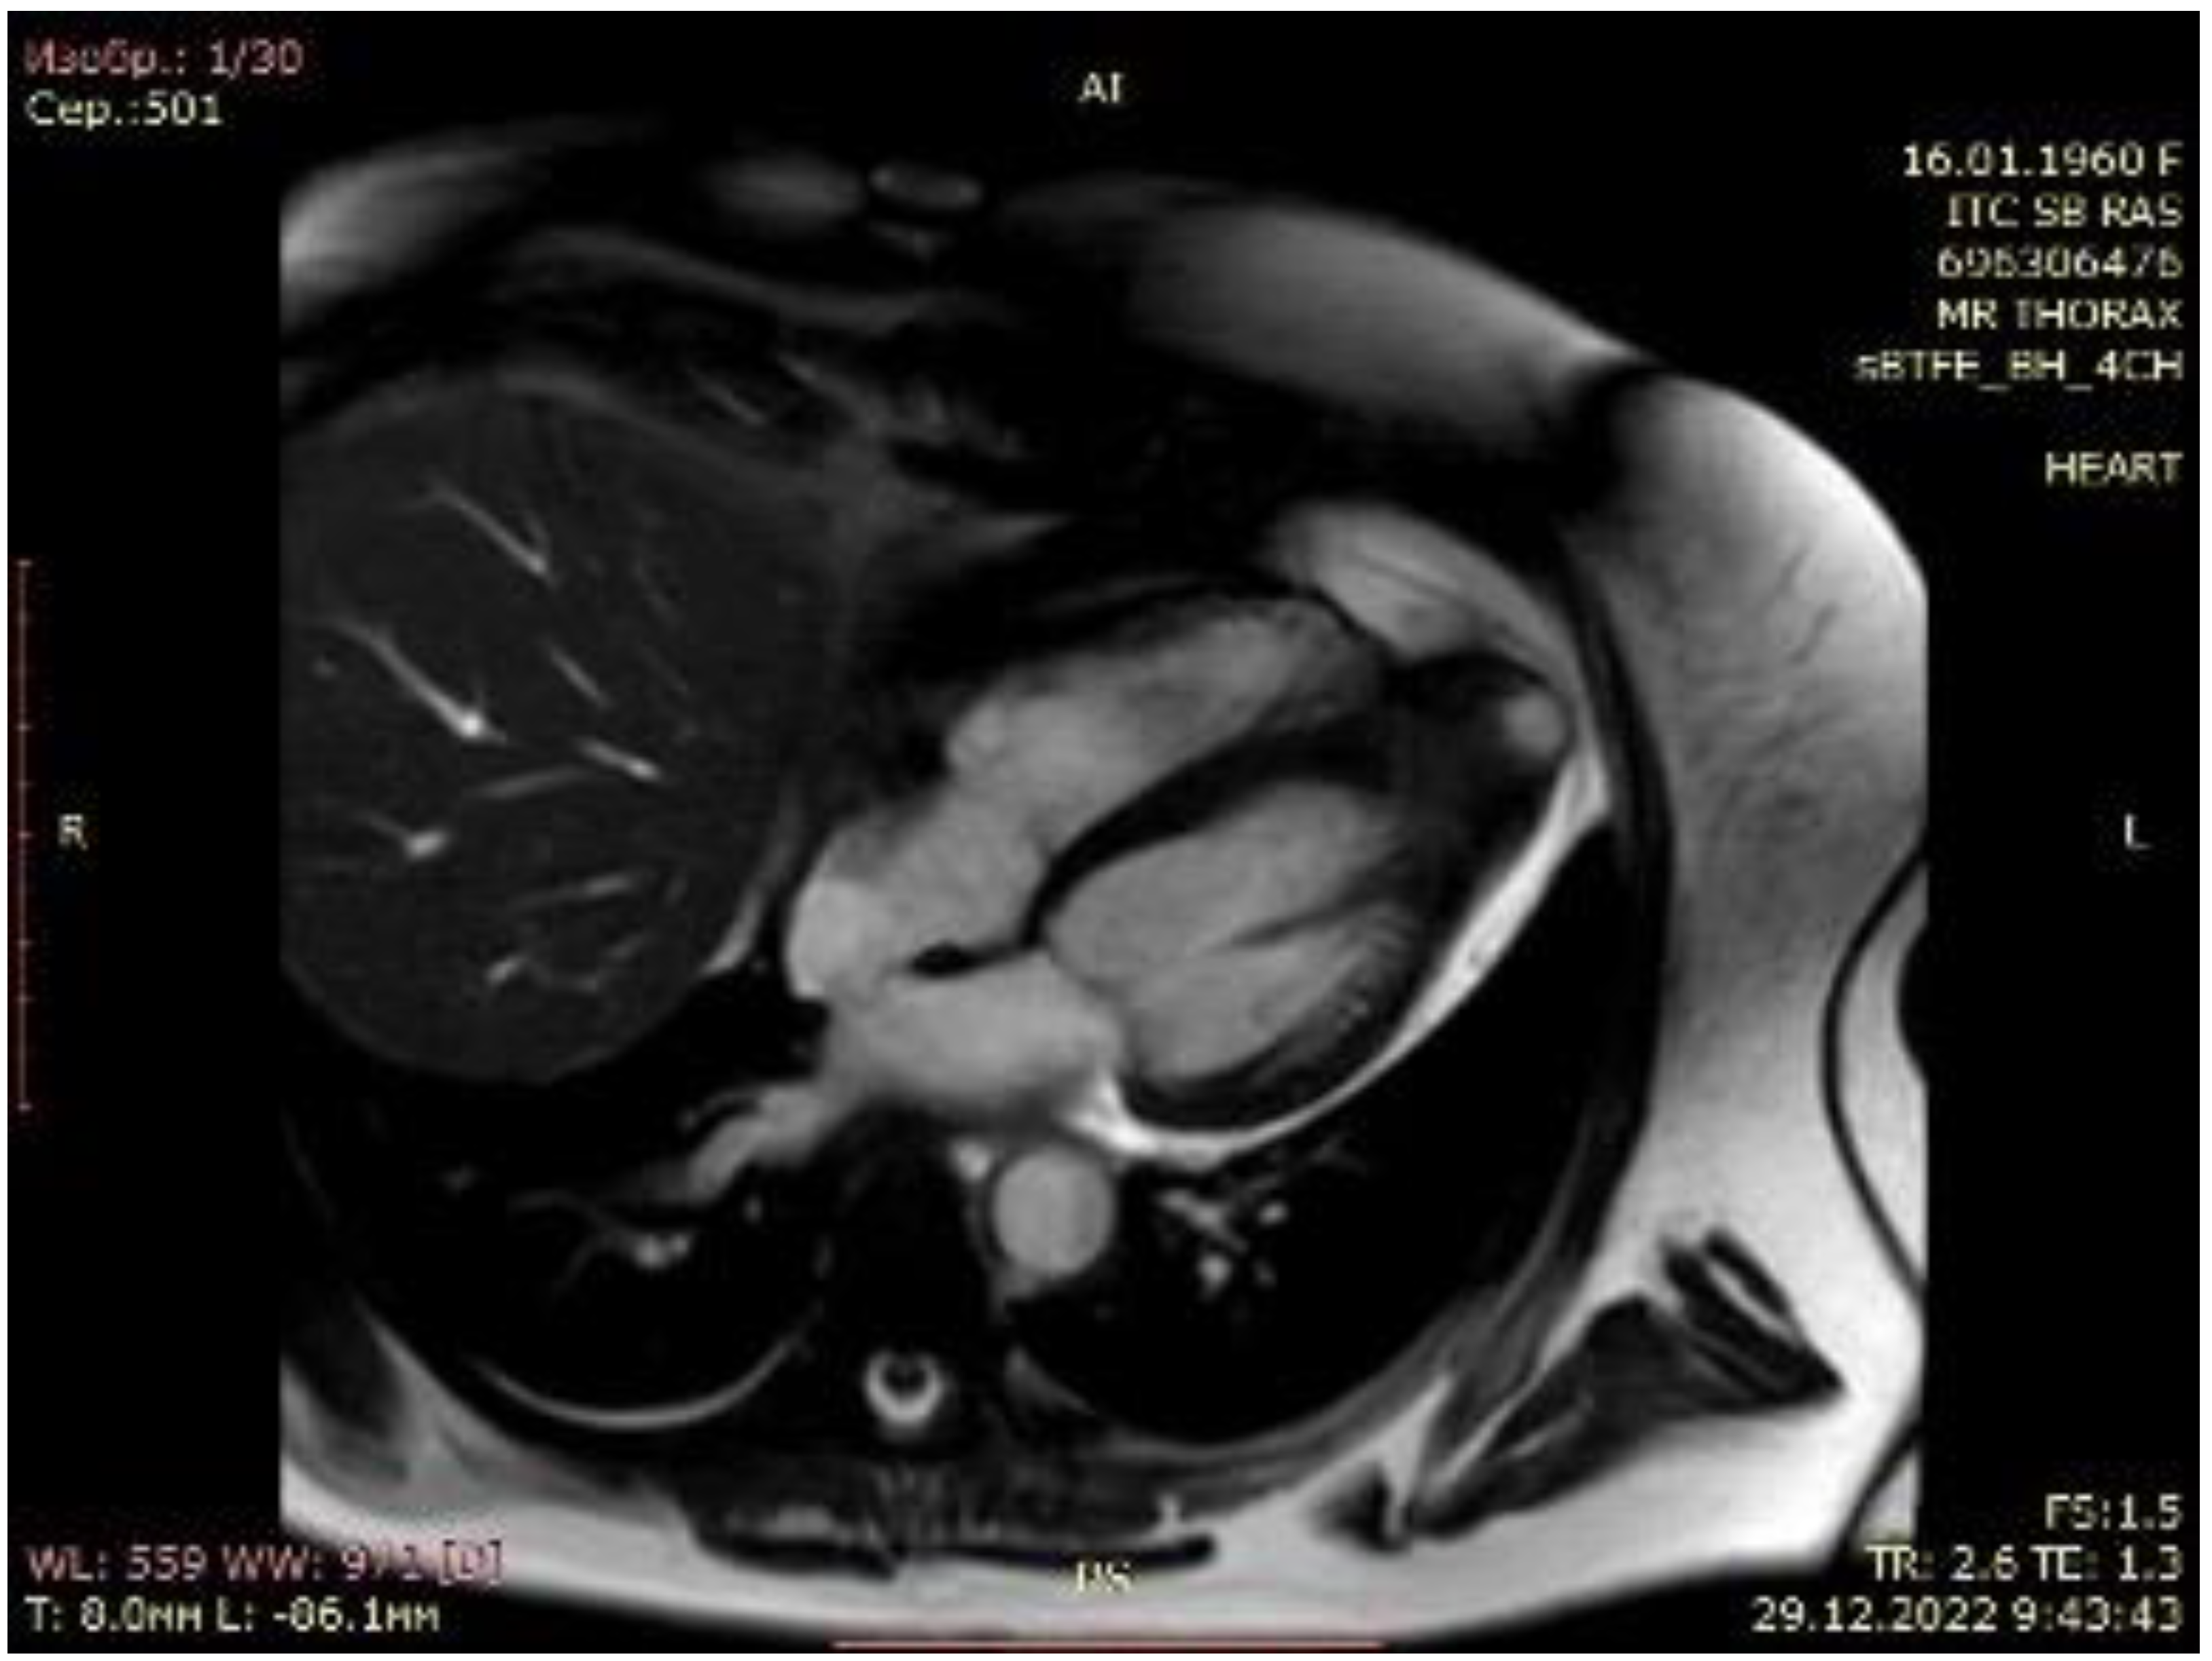

Figure 2.

Cardiac magnetic resonance imaging of patient with apical hypertrophic cardiomyopathy.

A 63-year-old female with marked limitations in daily activities, fatigue, and shortness of breath while walking a short distance (approximately 50 m) was admitted to the hospital and diagnosed as New York Heart Association (NYHA) class III-IV. An electrocardiogram showed high QRS voltage and negative T waves in the precordial leads. Transthoracic echocardiography revealed an apical HCM variant with a left ventricular end-diastolic volume (LVEDV) of 59 mL, increased left atrial volume index of 44 mL/m2, average E/e’ > 14, LV ejection fraction (LVEF) of 69% without LVOTO (maximum exercise provokable LVOT gradient 15 mmHg), a reduced stroke volume (SV) index of 22 mL/m2, Grade 1 (mild) mitral regurgitation findings, and no systolic anterior motion syndrome. There was no evidence of subaortic obstruction. The maximum septal thicknesses in the basal, midventricular, and apical parts were 15, 15, and 19 mm, respectively (Figure 1, Supplementary Video S1). Coronary angiography revealed a right-dominant circulation without pathological outlines. A cardiac MRI confirmed apical HCM with maximum septal thicknesses in the basal, midventricular, and apical parts of 9, 14, and 20 mm, respectively; maximum LV lateral wall thicknesses of 6, 6, and 21 mm, respectively; maximum LV posterior wall thicknesses of 5, 6, and 18 mm, respectively; and maximum LV anterior wall thicknesses of 6, 6, and 18 mm, respectively (Figure 2, Supplementary Video S2).